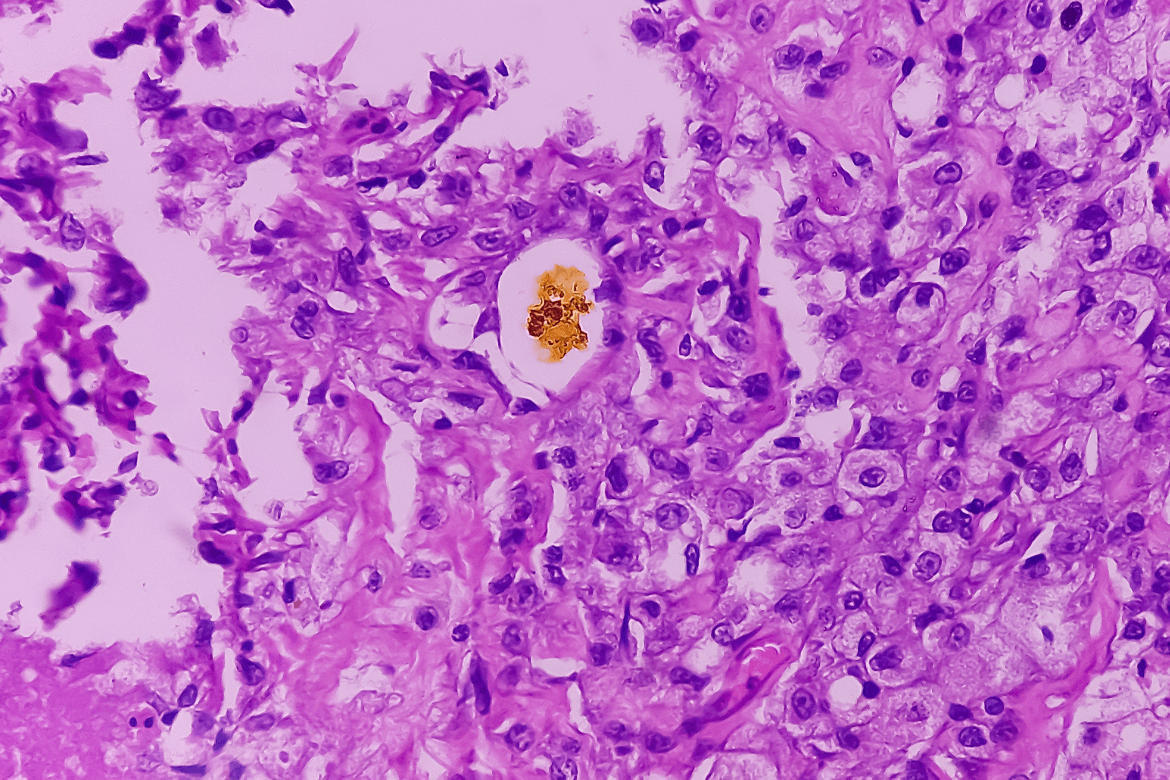

El crecimiento incesante de células plasmáticas no sólo desplaza a otros glóbulos blancos (linfocitos) de la médula ósea, sino que también puede formar tumores (plasmacitomas) en otras partes del organismo, por fuera de los huesos. Algunos pacientes desarrollan complicaciones a nivel neurológico, cardíaco o renal.

El mieloma múltiple recaído o refractario (que no responde a un tratamiento) constituye hoy un desafío para la supervivencia de los pacientes, ya que los fármacos habituales dejan de funcionar y las células plasmáticas se descontrolan al punto de generar tumores en distintos órganos, además de en los huesos.

Cuando solo hay un tumor, la enfermedad se llama plasmacitoma. Cuando hay muchos tumores, se llama mieloma múltiple. Para estos casos, hoy se están investigando nuevas inmunoterapias, como los anticuerpos biespecíficos teclistamab, talquetamab, elranatamab, y también terapias con células CAR-T.